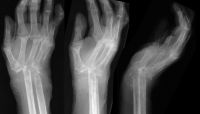

This senior woman presented with wrist swelling. She had been previously managed elsewhere with a Swanson flexible wrist arthroplasty, complicated by infection, which was treated with implant removal. She had done well for the last four years, but recently had swelling and tenderness of the wrist. Xrays showed a flail wrist with radiometacarpal impingement:

Four years later, she complained of wrist instability, and xrays confirmed intermittent radiometacarpal dislocation.

Highslide

She was treated with wrist arthodesis, using a sculpted fresh frozen femoral head allograft and a cerclage reinforced plate and screw fixation.

Late result, showing graft incorporation and remodelling.